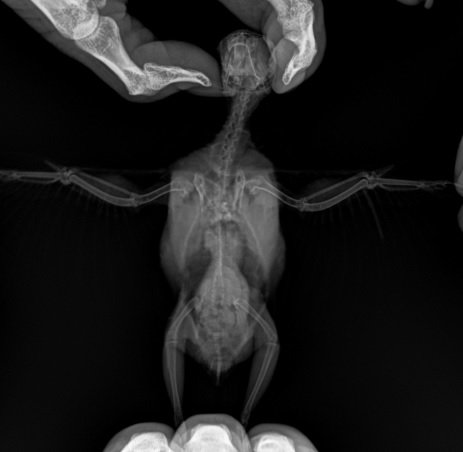

Паразиты на рентгеновских снимках - фото презентация